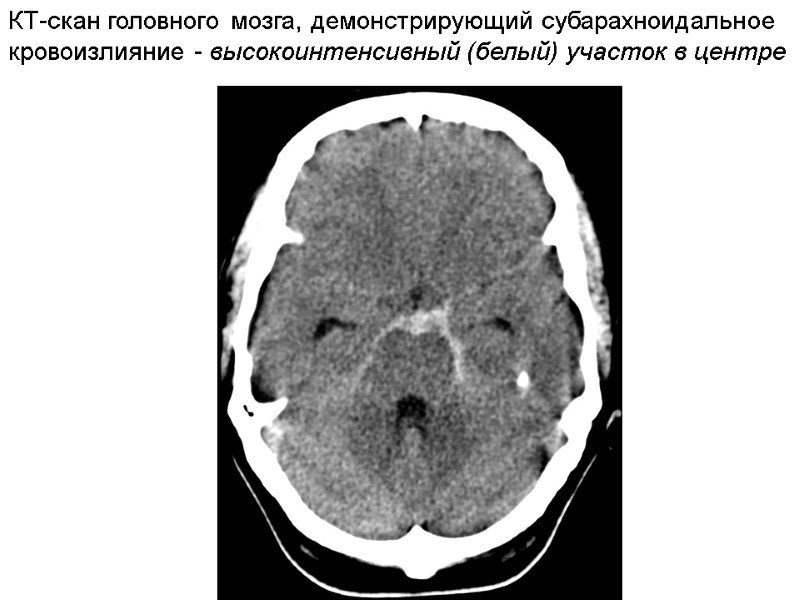

Вторая фаза проявляется при действии легкового автомобиля, когда центр тяжести тела пострадавшего находится выше места соударения. При фронтальном столкновении тело забрасывается на капот автомобиля. При этом повреждения образуются на той же поверхности тела, что и в 1 фазе. Отмечаются ссадины, кровоподтеки, реже – ушибленные раны мягких тканей головы, спины, груди и живота. Оскольчатые переломы костей свода и основания черепа, ушибы головного мозга, которые возникают как в месте удара, так и в области противоудара. Отмечаются закрытые переломы ребер, как локальные, так и конструкционные (непрямые), возникающие от деформации изгиба. В 1 и 2 фазах часто возникают повреждения внутренних органов. Вследствие ударного воздействия – кровоизлияния под капсулу и паренхиму органов, надрывы и разрывы органов грудной клетки и живота (корни легких, разрыв интимы крупных сосудов сердца, брызжейки, ворота почки и селезенки, печени) – локализуются всегда вблизи места приложения силы. Повреждения, вследствие сотрясения тела, морфологически выражаются в надрывах и разрывах связочного аппарата и сосудов, проходящих в них, кровоизлияния под капсулы и паренхиму органов. При очень сильных ударах (скорость автомобиля более 100 км/ч) – отрывы и размозжение внутренних органов, в т.ч. легких. В 3 фазе (отбрасывание тела и падение на грунт) образуются ссадины, кровоподтеки, рвано-ушибленные раны мягких тканей, в т.ч. на другой стороне тела, нежели в 1 и 2 фазах; переломы, в т.ч. костей черепа. В 4 фазе (скольжение и трение тела по грунту) – обширные, полосчатые ссадины (вдоль движения) – по которым можно установить направление движения; стертость мягких тканей и костей, которые располагаются на выступающих частях тела; на одежде – истончения, разрывы - поперечные, по отношению к направлению движения.